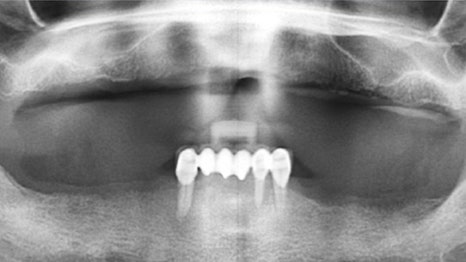

사례 3

교정 유지 장치를 활용한 임플란트

17개 임플란트를 권유받고 방문한 환자분의 경우,

치주 치료 후 앞니 흔들림이 개선되어 발치하지 않고

교정 유지 장치 를 활용하여 보완하였습니다.

기존 보철물을 제거하고 11개의 임플란트를

식립하여 치료를 마무리했습니다.